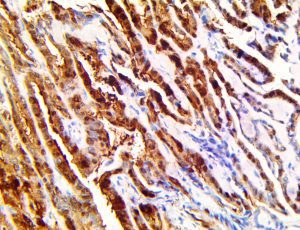

This activation induces inflammatory monocytes to highly express IL-6, starting a localized and then systemic cascade effect that results in hyperproduction of IL-6, which accelerates the inflammatory process. Because IL-6 also increases vascular permeability, excessive levels cause blood vessels to become very leaky. This, along with clotting factors released from vascular endothelial cells, stimulates the coagulation cascade, resulting in microthrombosis (tiny clots), which leads to ischemia and tissue death of the kidney, intestines, heart, liver, brain and extremities.